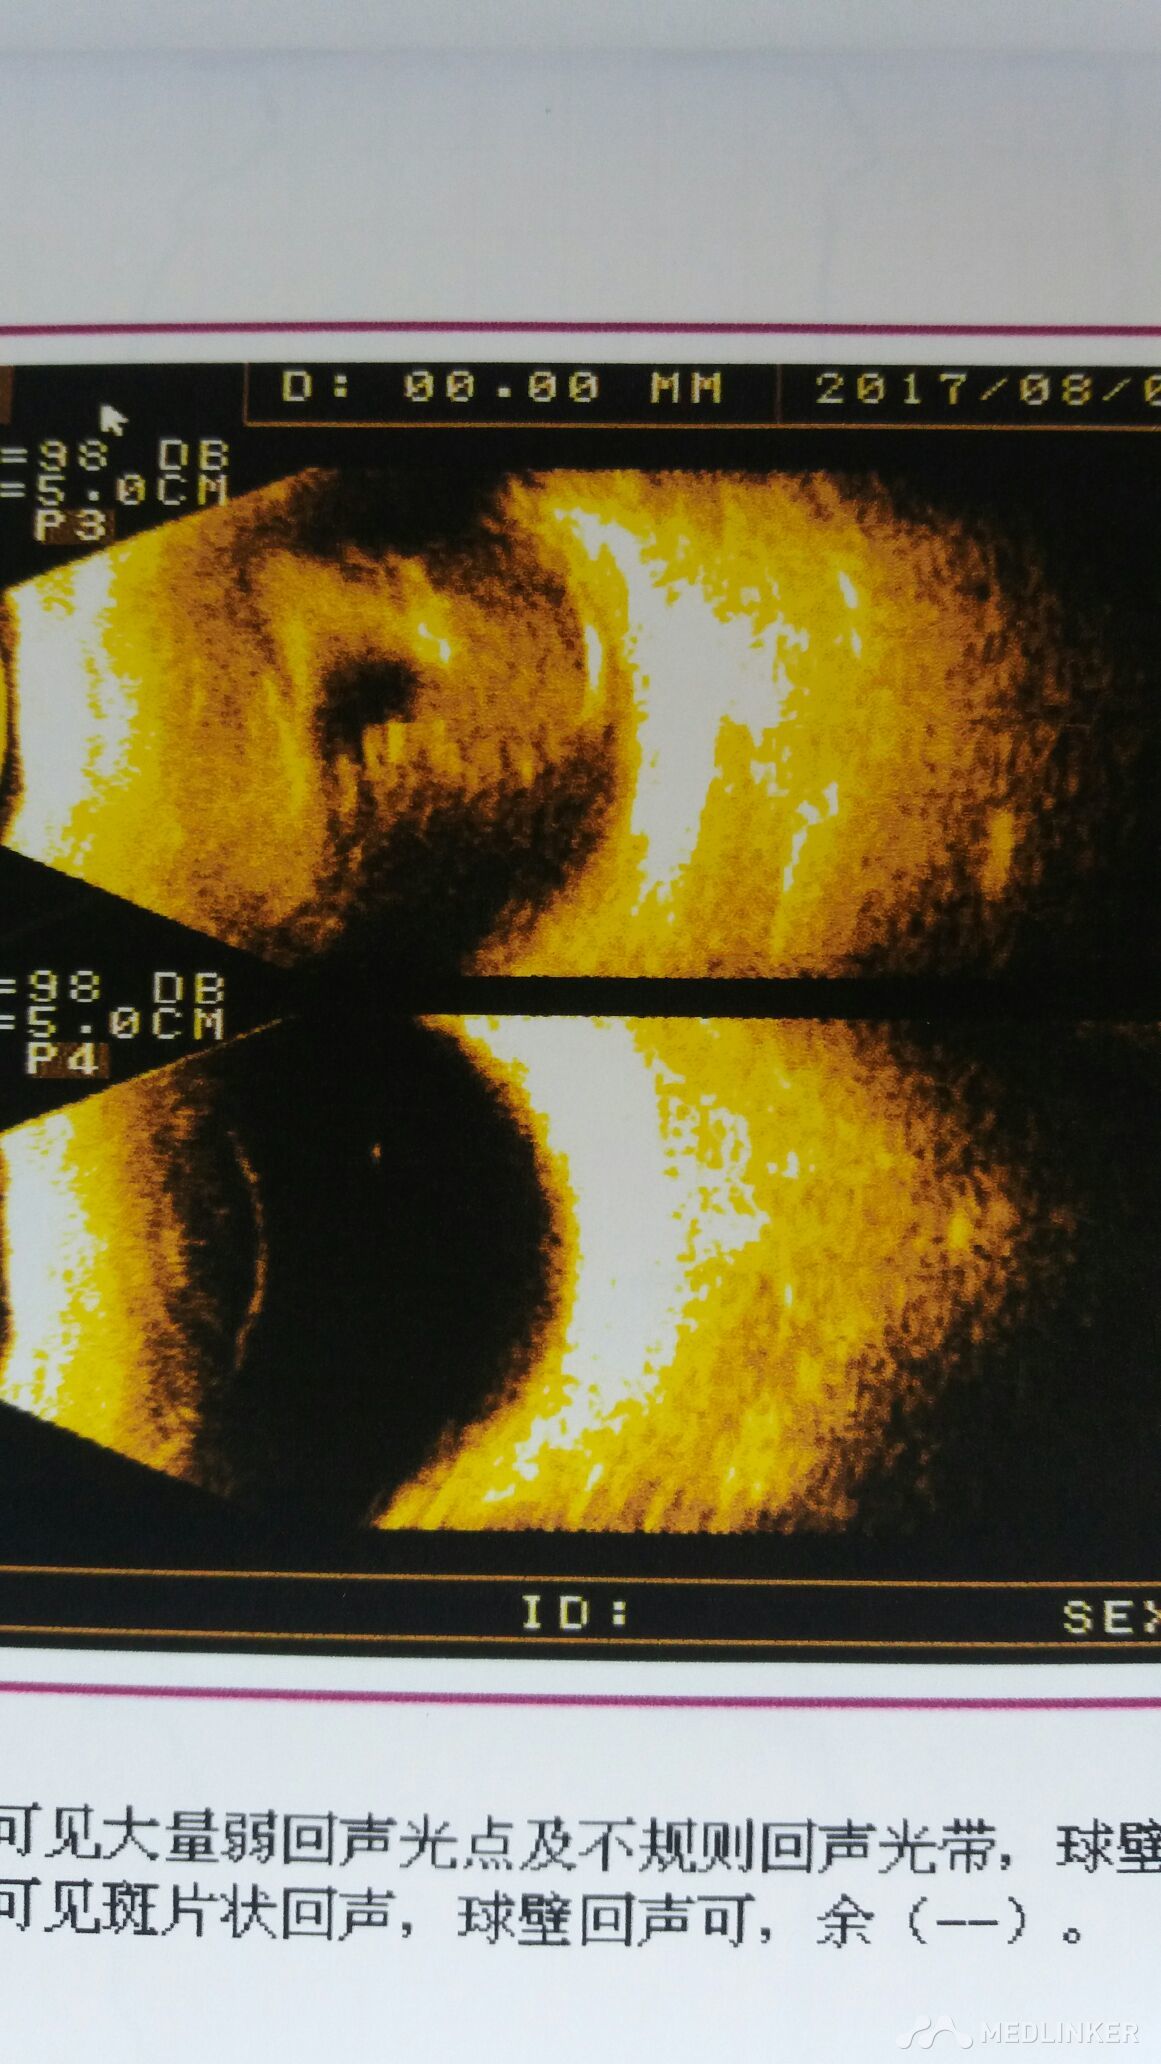

眼球破裂伤

这样的眼球破裂伤怎么处理好?

右眼眼球破裂

关于出现眼球破裂伤这种情况的处理。